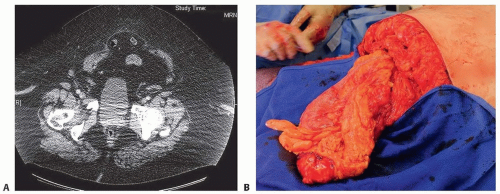

If hernia is suspected, CT scan with contrast is warranted (FIG 1).

Indications for surgery include overhanging panniculus interfering with ambulation and undergoing combined abdominal operations (eg, hysterectomy, tumor extirpation, hernia repair; FIG 2).